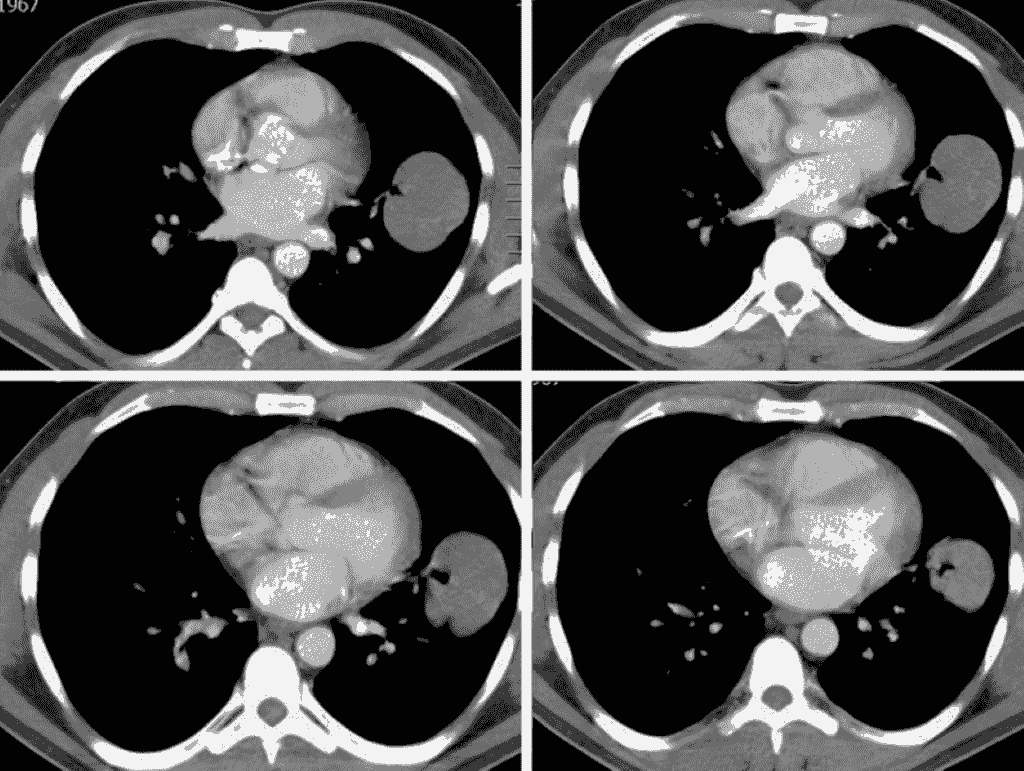

Section image

Tomografía Computada Toráxica

Ideal para examinar enfermedades pulmonares, como cáncer

de pulmón, infecciones o enfermedades

pulmonares intersticiales.

Saber mas...